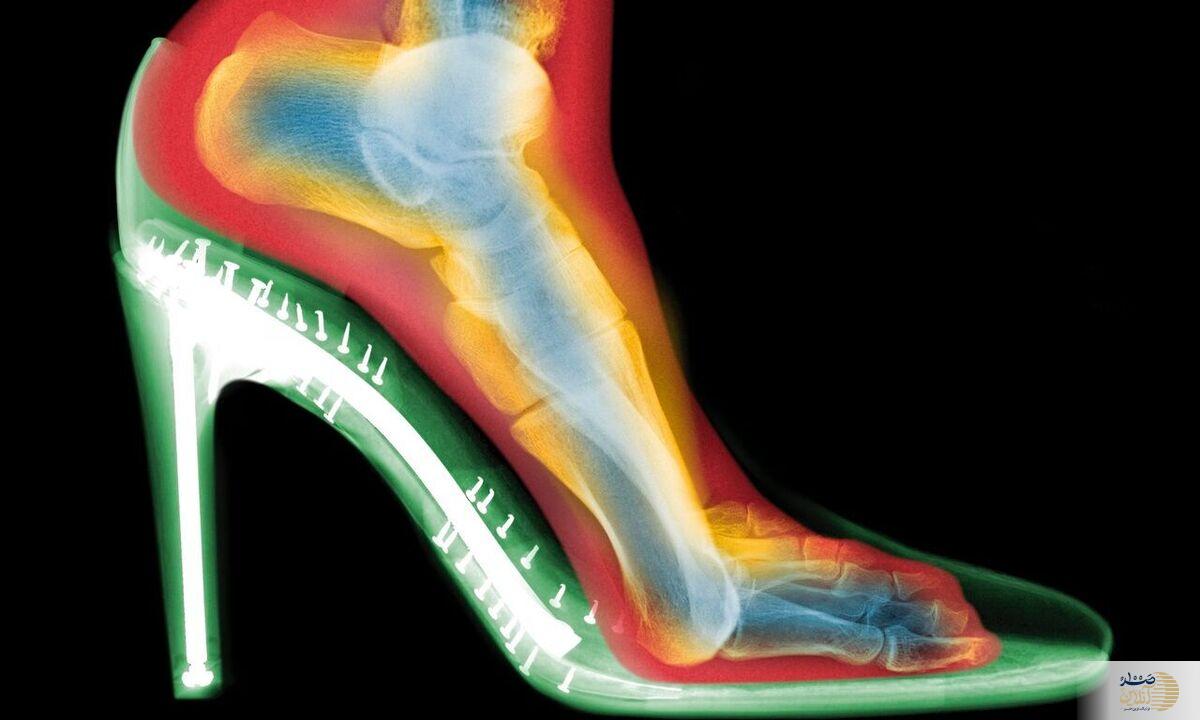

صد آنلاین | پوشیدن مداوم کفش‌های پاشنه‌بلند می‌تواند به تغییر شکل دائمی پا، ایجاد قوز شست و آرتروز منجر شود. یک متخصص ارتوپد که پیش‌تر این ایده را رد می‌کرد، امروز با مشاهده اسکن‌های سه‌بعدی هشدار جدی می‌دهد.

اسکن‌های سه‌بعدی چه نشان دادند؟

گلدبرگ دو اسکن از پای یک فرد تهیه کرد: یکی بدون کفش و دیگری با کفش پاشنه‌بلند. تفاوت‌ها چشمگیر بود:

فشردگی انگشتان: انگشتان پا در کفش به هم فشرده شده بودند؛

انحراف شست پا (بونیون): مفصل انگشت شست به طرف بیرون متمایل شده بود؛

انگشتان چنگالی: انگشتان کوچک‌تر برای حفظ تعادل، حالتی قفل‌شده و خمیده به خود گرفته بودند.